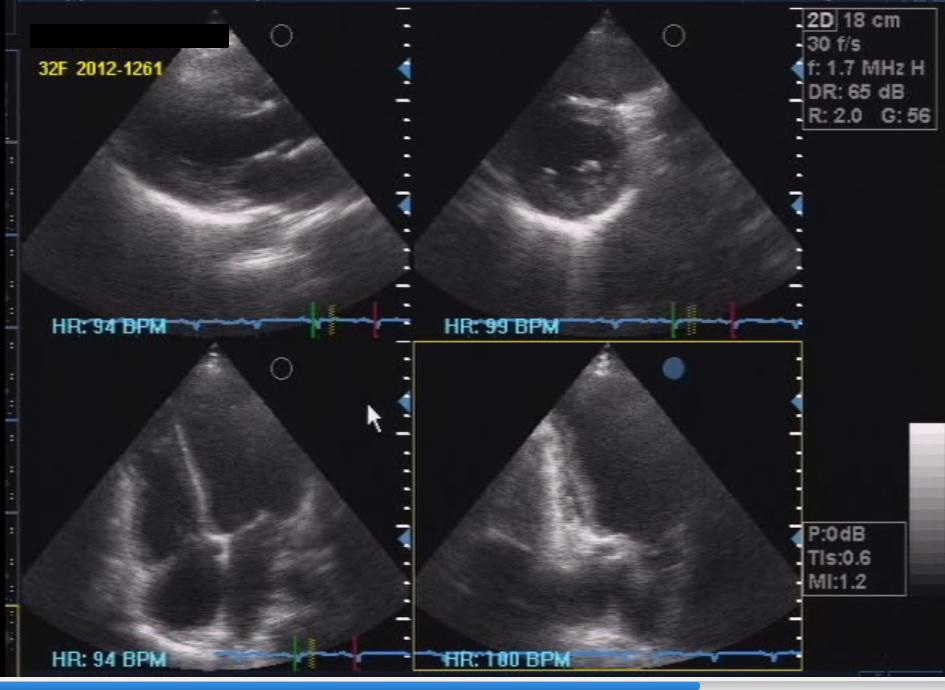

Two months after discharge, the patient underwent a repeat 2D echocardiogram (Figure 4) revealing the absence of the pericardial effusion but with pericardial thickening. There was also improvement of overall left ventricular systolic function after treatment with heart failure and anti-thyroid drugs. The patient went into preterm labor at 32 weeks of gestation. She delivered a live baby girl via spontaneous vaginal delivery, who was admitted to the neonatal intensive care unit and eventually discharged.

Click here to download Figure 4Figure 4. Repeat 2D echocardiogram after two months, showing absence of pericardial effusion but with thickened pericardium.